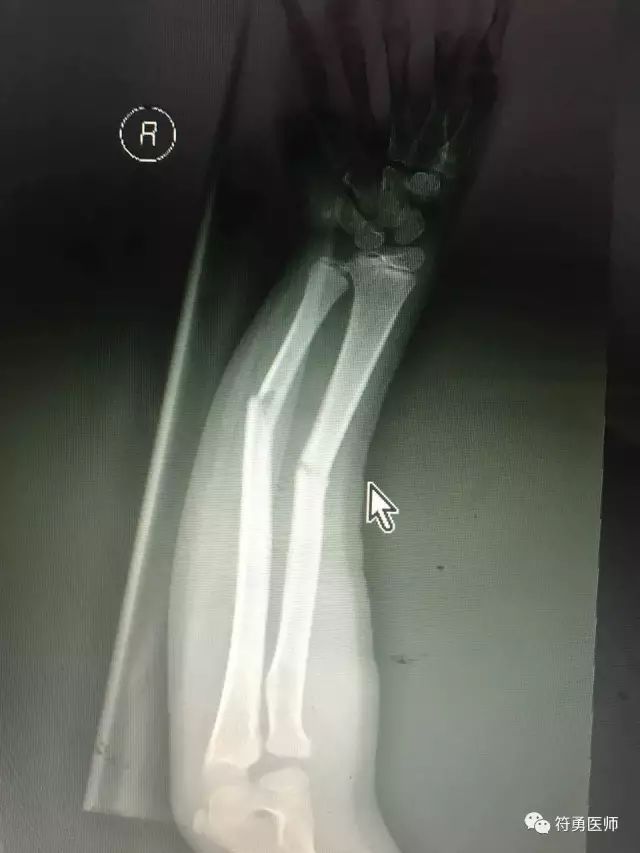

上图:摔伤后第二次找外院的医生接骨后正位好转,孩子受罪疼痛折腾,但看看下图的侧位仍然位置不理想

上图:摔伤后第二次找外院的医生接骨后正位好转,孩子受罪疼痛折腾,但看看上面的侧位仍然位置不理想。